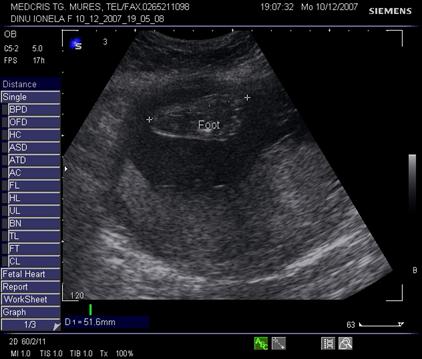

Piciorul trebuie evidentiat in continuarea gambei in sectiune sagitala. Aspectul plantar cu 5 degete, se obtine prin rotatia cu 90% a transductorului, dar necesita timp pentru imagine corecta. Planta nu poate fi evidentiata in asociere cu tibia, decat in prezenta unei deformitati ale membrelor.[1,7,12]

Fig. nr. 193. Membre inferioare in usoara flexie la 16 sapt. gestationale, cu linie tibia, se remarca la membrul inferior din planul departat de sonda ecografica, doua oase la gamba, hiperecogene si paralele

Fig. nr. 194. Talpa la 25 sapt. gestationale

Centrii de osificare ai calcaneului, talus, metatars, falange incep la 22 saptamani sa fie evidentiati ecografic.